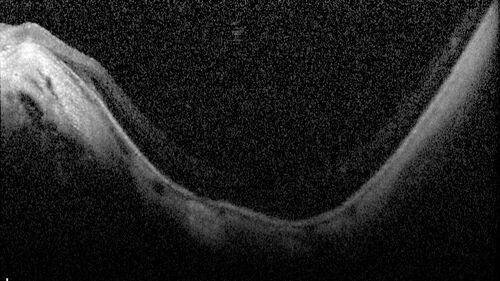

Stable Myopic Tractional Maculopathy

73 year old female with mild vision loss from table myopic tractional maculopathy in the left eye